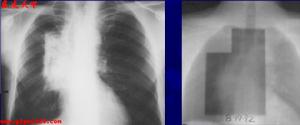

肺功能改變:肺放射性肺炎和纖維化都引起限制性通氣功能障礙,肺順應性減低,伴通氣/血流比例降低和彌散功能減低,導致缺氧。有時胸片尚未發現異常,而肺功能檢查已顯示變化。 X線表現:多數於停止放療一月後,肺部出陰影。急性期在照射的肺野上出現彌溫性片狀模糊陰影,其間隱約可見網狀影,酷似支氣管肺炎或肺水腫。病變的範圍與胸廓表面照射野一致。慢性發生肺纖維化,呈條索狀或團塊狀收縮或局限性肺不張。縱隔胸膜和心包有大量粘連,縱隔向患側移位,同側橫膈升高和胸廓塌陷。

放射性肺炎“放射性肺炎”的診斷一般並不複雜,可根據如下依據進行診斷:有放射性治療史;病人有乾性嗆咳、進行性氣急及肺部的Velcro羅音具有特徵性;胸部X線檢查可見肺部炎症或纖維化表現。多於停止放射治療一個月後出現。急性期表現為在照射肺野出現片狀或溶合成大片、緻密的模糊陰影,其間隱約可見網狀陰影,與支氣管肺炎或肺水腫極為相似。慢性期表現為肺纖維化,呈網狀,條索狀或團塊狀收縮陰影,主要分布於肺門或縱隔兩側及其他放射肺野。由於肺纖維收縮,氣管、心臟向患側移位,同側橫膈抬高,正常肺組織產生代償性肺氣腫。發生肺動脈高壓時,表現為肺動脈段突出或右心肥大。常有胸腔積液特徵。特別注意的是需與肺轉移性癌相鑑別,如果將放射性肺部損傷誤作為肺轉移性腫瘤,繼續放療,可造成死亡。放射性肺損傷的部位一般與照射野相符,經過一段時間觀察肺纖維化後病灶會回縮,而轉移癌會繼續增大。為了預防放射性肺損傷的發生,應嚴格掌握放射野、時間和劑量,以儘量避免肺部的損傷。